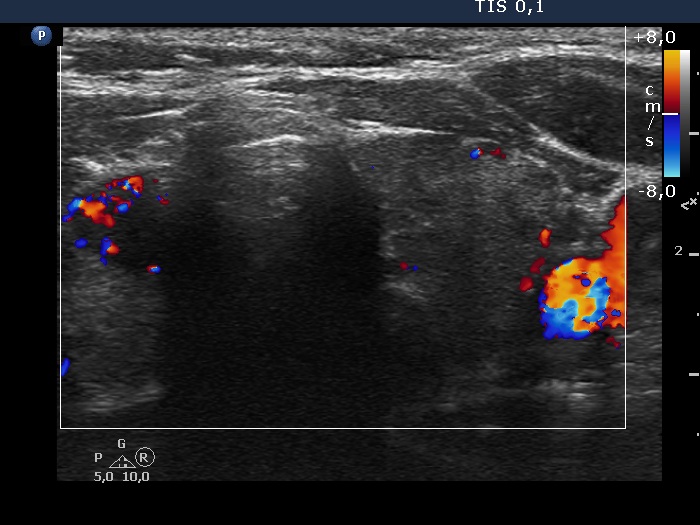

The shape of the nodule - case 2251 (ultrasonographic picture 6)

Left lobe, transverse view, color Doppler mode. The vascularization is not specific.